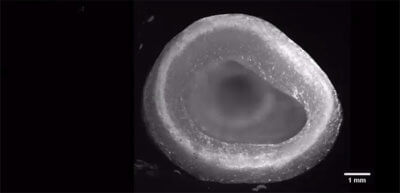

Die Mikrostrukturen menschlicher Gewebe und Organe lassen sich nicht so leicht nachbilden. Doch sie entscheidend, wenn es um die Funktion der Organe geht. Es ist schwierig, das zu Beginn der Prozedur noch flüssige Kollagen für das Grundgerüst in Form zu bringen. Die neue Methode von Andrew Hudson von der Carnegie Mellon University in Pittsburgh und seinem Team erlaubt feinste Mikrostrukturen aus Kollagen. So können die Forscher nun Organgerüste aus Kollagenfasern von nur 25 Mikrometern Dicke drucken. Zellbesetzte Organteile wurden mit der FRESH (Freeform Reversible Embedding of Suspended Hydrogels) getauften Methode angefertigt.

Das Bad in zähem Hydrogel beim 3D-Druck sorgt für winzige Kollagenstrukturen, die nicht aus der Form geraten und Hohlräume und Poren gedruckt werden können. Durch die Verkleinerung der Moleküle auf 25 Mikrometer nimmt die Auflösung der Teile zu. Ist der Druck fertig, härtet die Kollagenlösung aus. Das Organmodell wird erwärmt, wodurch das Hydrogel wegschmilzt. Die FRESH-Methode sorgt dafür, dass auch komplette Organteile, dessen Zellen, biologische Materialien und feinste Verästelungen von Gefäßen möglich sind.